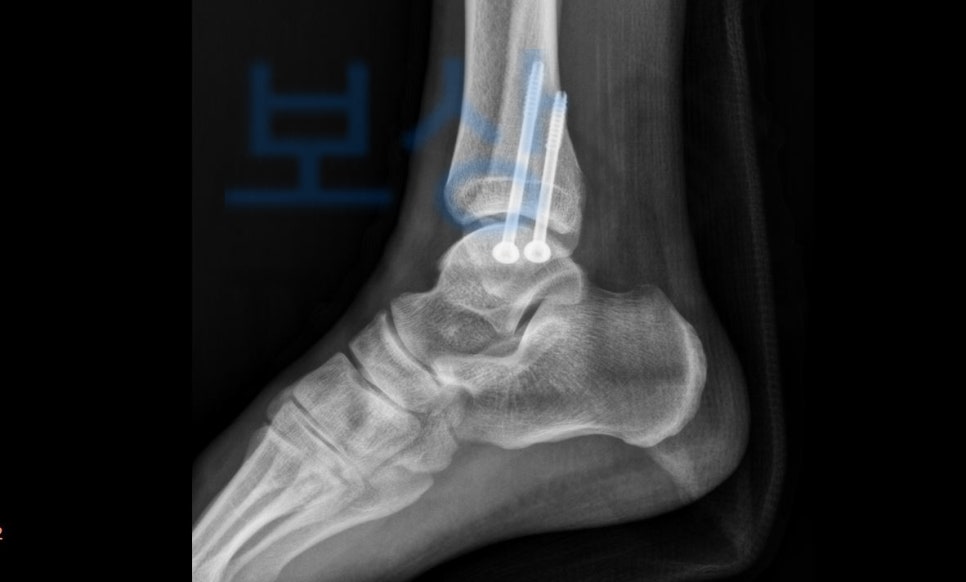

이 사고로 황@@님은

양측 복사 골절, 발목, 폐쇄성 S82820

진단을 받아 금속고정술을 받아 6주간의 안정이 필요하셨죠.